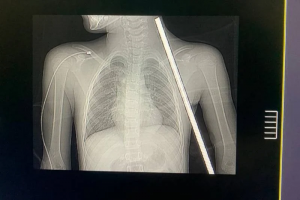

IMG_2614

Foto: Reprodução